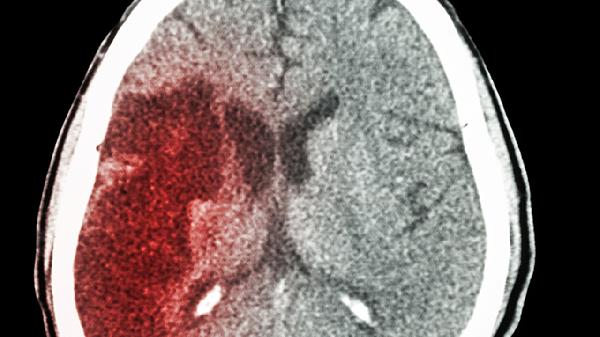

如果出血量在10毫升以内,通常恢复情况比较乐观,患者可能只会有轻微的头痛或头晕。但如果出血量超过30毫升,就可能对脑组织造成压迫,这时候就需要通过CT来持续观察变化。

2、出血部位:

比如脑干或丘脑这些关键区域,即使少量出血也可能影响到呼吸和循环系统。而大脑皮层出血则相对风险小一些。如果是在基底节区出血,可能会出现肢体无力等局部神经功能障碍。